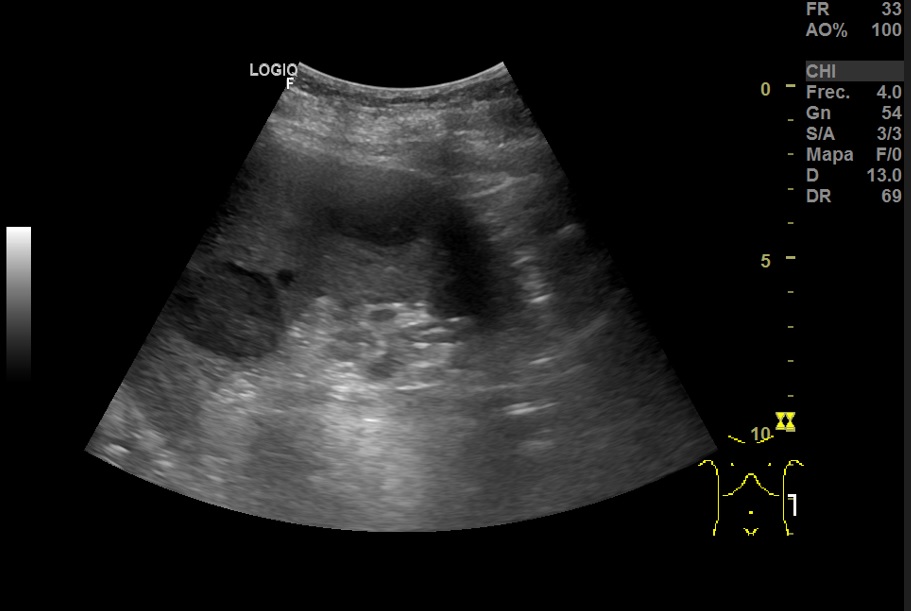

Hallazgos ecográfico: Esplenomegalia y varias lesiones focales hipoecogénicos de diferentes tamaños de bordes bien definidos en el bazo.

TAC abdominal: Bazo con múltiples imágenes hipodensas focales, mal delimitadas. Múltiples adenomegalias retrocrurales, mesentéricas, esplénicas y retroperitoneales.